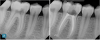

Figure 1 and Figure 2 provide examples of some cases that the author treated using the single-visit endo-restorative workflow. Despite the complex or challenging anatomy shown in these radiographs, the canals were able to be thoroughly irrigated by the multisonic irrigation system that was used with this workflow. For these cases, the one-day treatment workflow and the use of multisonic irrigation as described in this article enabled successful root canal treatment and improved patient satisfaction.

Fig 1 Using the endo-restorative workflow described in this article, the complex anatomy shown in these radiographs was able to be irrigated by multisonic

irrigation. Fig 1, left panel: Preoperative radiograph of tooth No. 14 with acute periapical abscess and dental caries in a 20-year-old male patient with good dental

and overall health. A filling had broken, and the patient had postponed treatment. Fig 1, right panel: Postoperative radiograph (after the single-visit endo-restorative

Figure 1